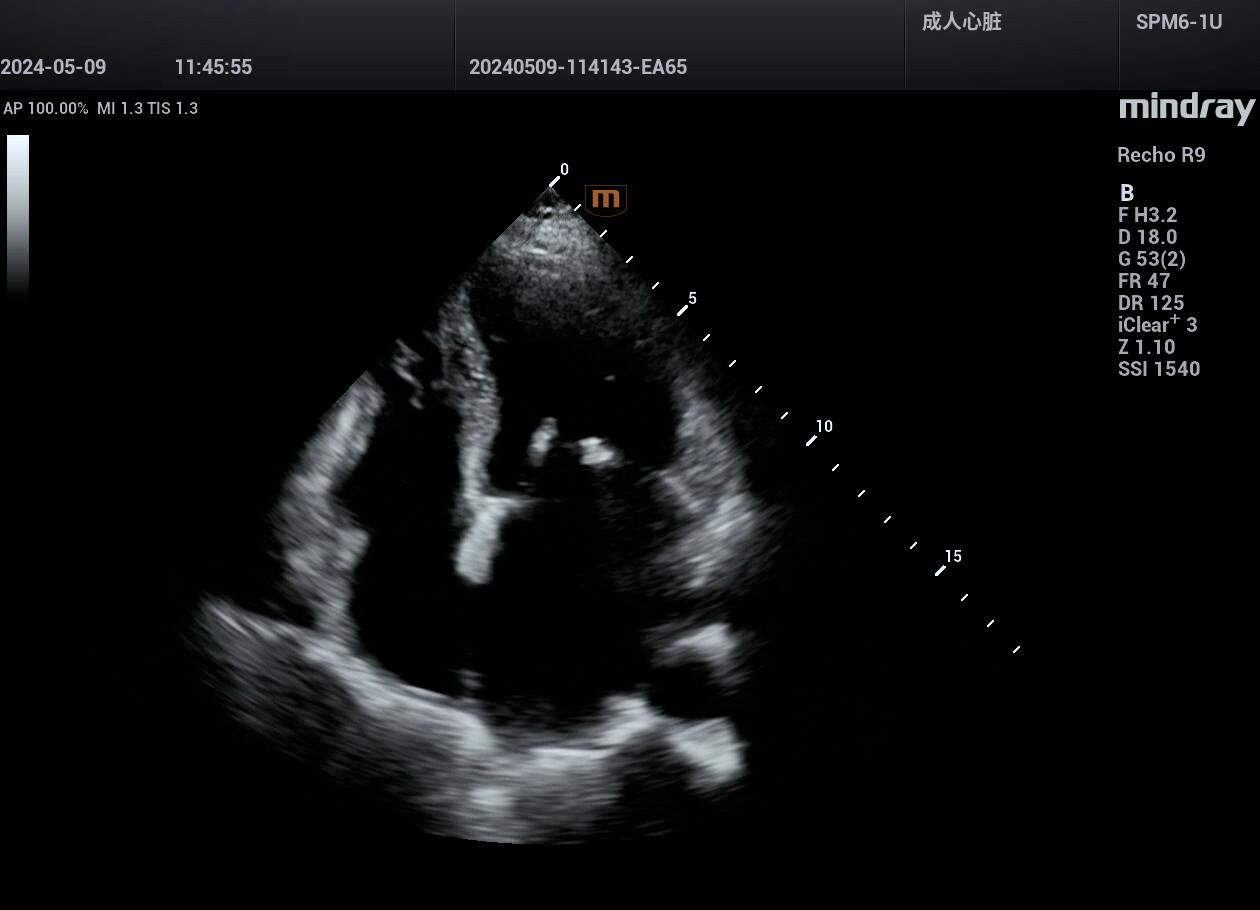

病例,肥厚梗阻性心肌病,10岁小孩,典型病例。迈瑞Recho R9,2024年3月

高端心脏超声迈瑞Recho R9,实现县县超声事业的高质量发展!